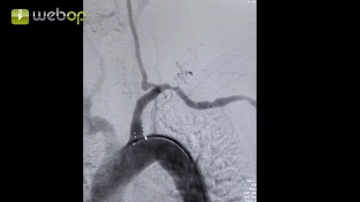

Angiografía

Ajustes de sonido Representación de las ramas supraaórticas, en particular de la arteria subclavia izquierda. Marcado del origen de la arteria subclavia del arco aórtico así como de su estenosis.

1. Para una mejor representación de las ramas supraaórticas en pacientes despiertos, se debe hacer que el paciente respire profundamente primero, inhalando y exhalando, posteriormente se realiza la angiografía durante una pausa respiratoria.

2. El arco aórtico debe representarse anatómicamente correcto. Para ello, el arco en C debe posicionarse en LAO entre 30 y 50° (proyección LAO = left anterior oblique, posición oblicua anterior izquierda).